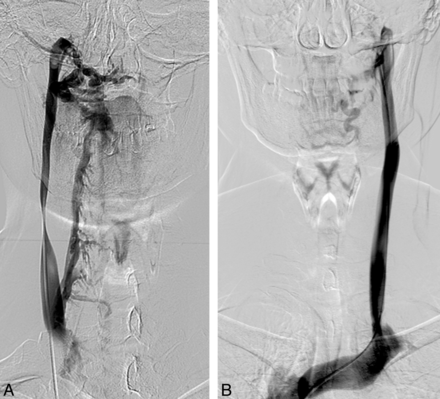

Given our data, we believe that with venography it is not possible to define a pathologic condition characterized by the presence of a reduced blood drainage from the CNS as the result of stenotic alterations or venous malformations of the neck and thorax, which definitely correlates with MS. In our opinion, 1 of the major limitations of venography in the evaluation of CCSVI may be the lack of standardization in the interpretation of the images, which therefore tends to be operator-dependent, especially when no blood pressure gradient is associated with morphologic alterations. In our series, only 6 patients presented with the complete occlusion of 1 or both IJVs with the evidence of voluminous collateral drainage (Fig 6), and in only 1 case the stenosis of the AV was associated with rachidian drainage. However in all of these cases, no significant blood pressure gradient was recorded. In the remainder of our population, the interpretation of venograms could have been influenced not only by the operator's experience but also several parameters of contrast media injection (volume, length, and site of injection) as well as patient breath dynamics.

Selective catheterization of the internal jugular veins bilaterally (A, -B) in a 27-year-old control subject. Complete obstruction of the IJVs bilaterally with evidence of venous outflow through collateral circulation in the external jugular veins is shown.